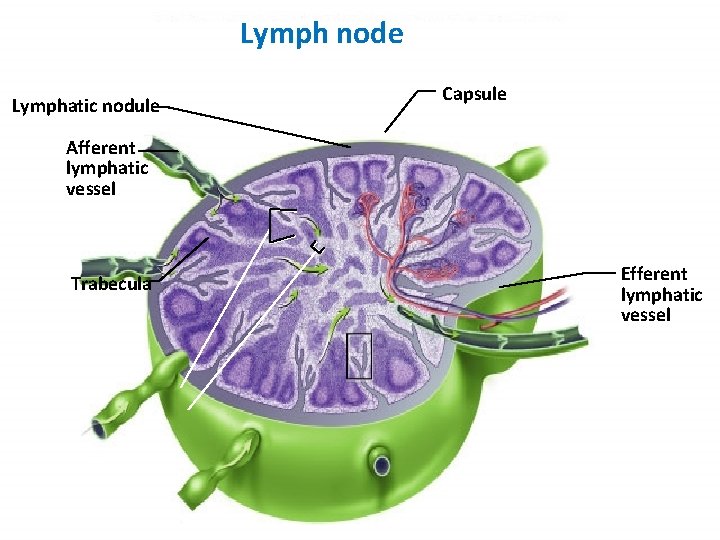

Lymph node Lymphatic nodule Fig. 22. 12 a(TECapsule Art) Afferent lymphatic vessel Trabecula Efferent lymphatic vessel

Lymph Node • • • Capsulated Afferent lymphatics “subcapsular sinus” Hilum – blood vessels, efferent lymphatic Cortex and medulla Cortex – Lymphatic nodules, germinal centres – “Paracortex” T-dependent zone • Medulla – Medullary cords and sinusoids M C

LYMPH NODES These are the smallest but most numerous encapsulated lymphoid organs. Scattered in groups along lymphatic vessels , they act as in-line filters of the lymph, removing antigens and cellular debris and adding Igs. Lymph nodes are bean-shaped structures with convex and concave surfaces. The parenchyma consists of a peripheral cortex, adjacent to the convex surface, and a central medulla lying near the depression (hilum) in the concave surface. The connective tissue capsule gives off trabeculae that penetrate between the cortical nodules and subdivide the cortex. Cortex. The cortex is dark-staining owing to the presence of tightly packed lymphocytes. These are suspended in a reticular connective tissue network and arranged as a layer of typical secondary lymphoid nodules (containing primarily B lymphocytes) with germinal centers. The cortex also contains reticular cells, antigen-presenting follicular dendritic cells, macrophages, a few plasma cells, and some helper T cells.

Medulla. Lighter staining than the cortex, the medulla is composed of cords of lymphoid tissue (medullary cords) separated by medullary sinuses. The lymphocytes are mainly small, less numerous than in the cortex. The cords are also rich in reticular cells and fibers and contain many plasma cells that have migrated from the cortex. Paracortical zone. This is the T-dependent region, lying between the cortical lymphoid nodules and the medulla. It contains mainly T lymphocytes suspended in a reticular connective tissue. B lymphocytes, plasma cells, macrophages, and antigen-presenting interdigitating dendritic cells may also be present. Lymphatic vessels. Sinuses (subcapsular, peritrabecular, medullary). Functions: 1. Filtration of lymph 2. Lymphocyte production (lymphopoiesis). 3. Immunoglobulin production.